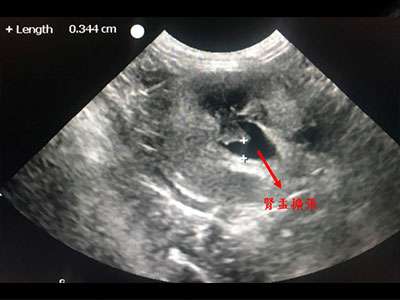

X光下動物泌尿道無明顯結石,超音波下發現膀胱壁增厚及發炎,腎盂、尿道擴張,膀胱內有大量結晶樣物質堆積。當下幫貓咪抽出70毫升之血尿,以緩解貓咪的疼痛不適、避免腎指數快速上升。